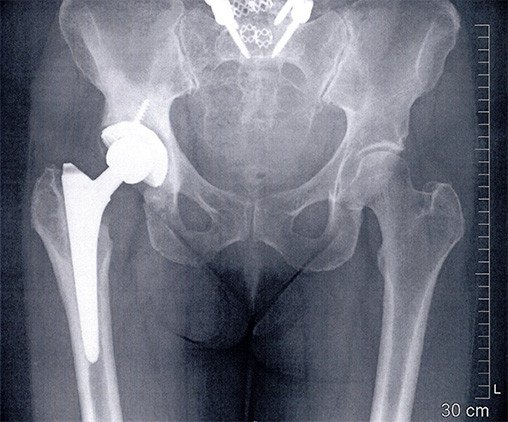

Bei der 56-jährigen Patientin wurde vor 8 Jahren rechts ein künstliches Hüftgelenk eingesetzt. Drei Jahre später stellte man eine frühe Lockerung der Pfanne fest, die ausgewechselt wurde. Bis vor einem Jahr mit günstigem Verlauf.

Seit einem Jahr hatte die Patientin erneut Hüftschmerzen. Die Abklärungen ergaben den Verdacht auf eine erneute Lockerung der Pfanne und allenfalls auch Schaftlockerung. Deshalb wurde sie erneut operiert. Intraoperativ zeigten sich klare Hinweise auf eine Infektion mit trübem Erguss. Die Hüfttotalprothese wurde daher komplett ausgebaut und die festsitzende Pfanne musste aus dem Becken herausgeschnitten werden. Der festsitzende Schaft konnte entfernt werden, nachdem der Oberschenkelknochen längs geschlitzt und aufgespreizt wurde.